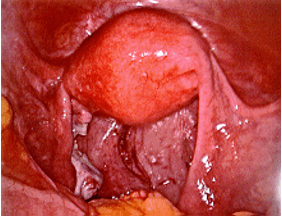

The photos below show several different types of ovarian masses:

Left photo – a large left ovarian dermoid tumor. The patient also has a uterus didelphys (2 separate uteri) connecting to a single cervix. Right photo – An incision has been made in the surface of the ovary.

Left photo – the dermoid tumor is almost out of the ovary. Right photo – A postoperative view after the dermoid has been removed. A large portion of the left ovary remains. This procedure was performed by laparoscopy allowing the patient to go home the same day.